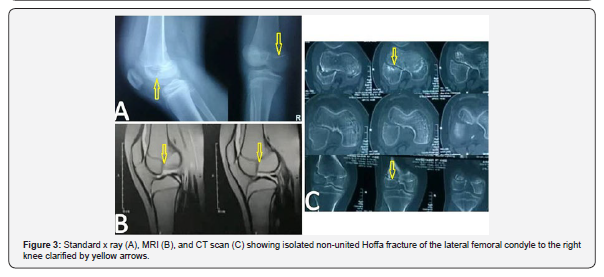

The purpose of this study was to present a rare case of missed coronal fracture of the lateral femoral condyle which is known as Hoffa fracture in a young adolescent complicated by pseudoarthrosis. In addition to review the literatures about previously reported non-union or pseudoarthrosis as a complication of this uncommon fracture in children and young adolescents. A 12-year-old patient presented to us 4 months after a motor vehicle accident with pain, swelling, and limping in his right knee. According to the patient family they went to a general hospital seeking for medical advice immediately after the trauma and x ray was done which have been evaluated by orthopaedic resident who decided for conservative management. Our Clinical examination revealed tender, swollen knee with antero-posterior instability which raise our suspicion for cruciate ligaments insufficiency (Figures 1 & 2). Radiological evaluation including standard x ray and CT scan showed isolated non-united Hoffa fracture of the lateral femoral condyle to the right knee (Figure 3). The fractured segment was about 2/3 of the lateral femoral condyle. MRI examination was done to evaluate cruciate ligaments and other intraarticular structures and showed no abnormalities except for the fracture. Therefore, we suggested that the antero-posterior instability that observed by clinical examination was due to instability at the fracture site of the lateral femoral condyle in which the femoral attachment of the ACL is present at the medial aspect of its postero-inferior portion. We decided for operative intervention without delay.